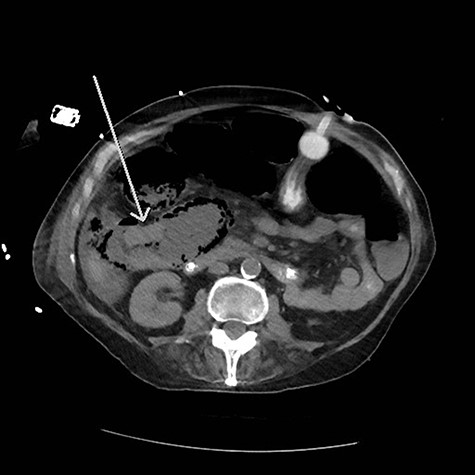

The patient’s post-operative course was complicated by dysphagia requiring gastrostomy tube placement. Surveillance imaging of the chest showed extensive mediastinal, hilar and supraclavicular lymphadenopathy with new pulmonary nodules and a large mediastinal mass encasing the trachea and ascending aorta consistent with distant metastatic disease. Cardiothoracic surgery was consulted and deemed the mass unresectable. On subsequent follow up, the patient endorsed a 2-year history of melena and was referred to gastroenterology for colonoscopy. However, prior to the scheduled colonoscopy, the patient was found to have abdominal distention with imaging confirming colonic pneumatosis and a large mass in the ascending colon. The patient’s clinical condition deteriorated despite non-operative management. He underwent exploratory laparotomy with right hemicolectomy, transverse colectomy and end ileostomy. Pathology workup included concurrent comparison of the salivary gland and colonic tumors, which showed similar histologic features. p63 and CK5/6 immunohistochemistry stain positivity in the colonic tumor confirmed the presence of SCC. CK20 and CDX2 immunostains to exclude a colonic primary adenocarcinoma or adenosquamous carcinoma were negative. In addition, due to the unusual initial presentation of a squamous appearing tumor in the submandibular gland, a MAML2 (11q21) rearrangement FISH study to rule out mucoepidermoid carcinoma (with squamous predominating features) was performed and was negative (Figs 3 and 4).